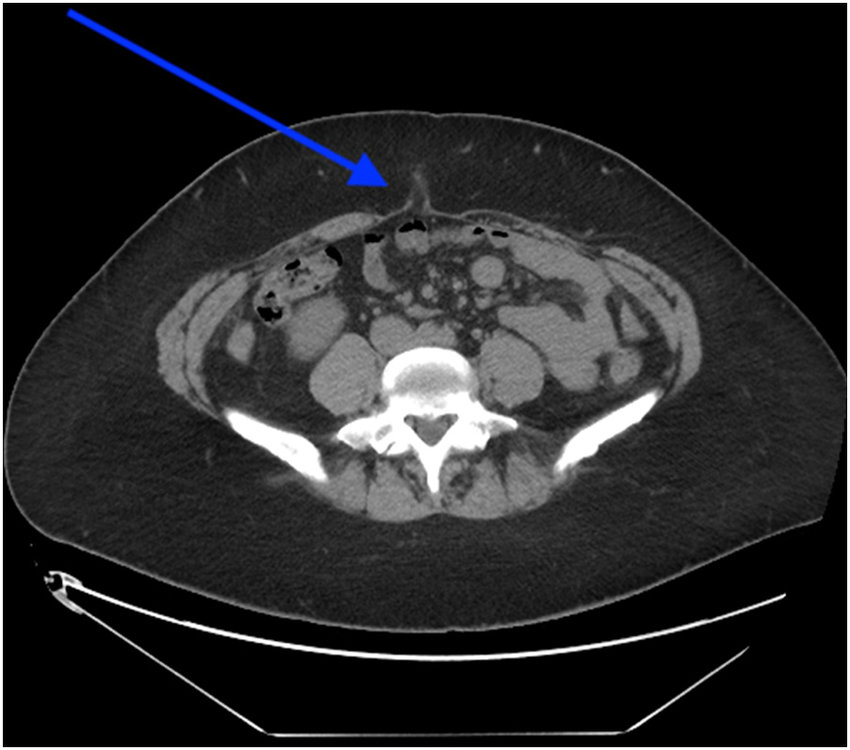

From www.researchgate.net

(PDF) Umbilical Hernias in Adults Epidemiology, Diagnosis and Treatment Kinesiology Tape For Umbilical Hernia Recently, kinesio taping (kt)—applying special tapes directly to the. Kinesio taping umbilical hernia and diastasis recti during pregnancy. Not sure who needs to see this but i have an umbilical hernia from my first pregnancy that’s just getting worse and worse this time. Buy your diastasis taping kit here. Although some people claim a hernia can be fixed by taping. Kinesiology Tape For Umbilical Hernia.